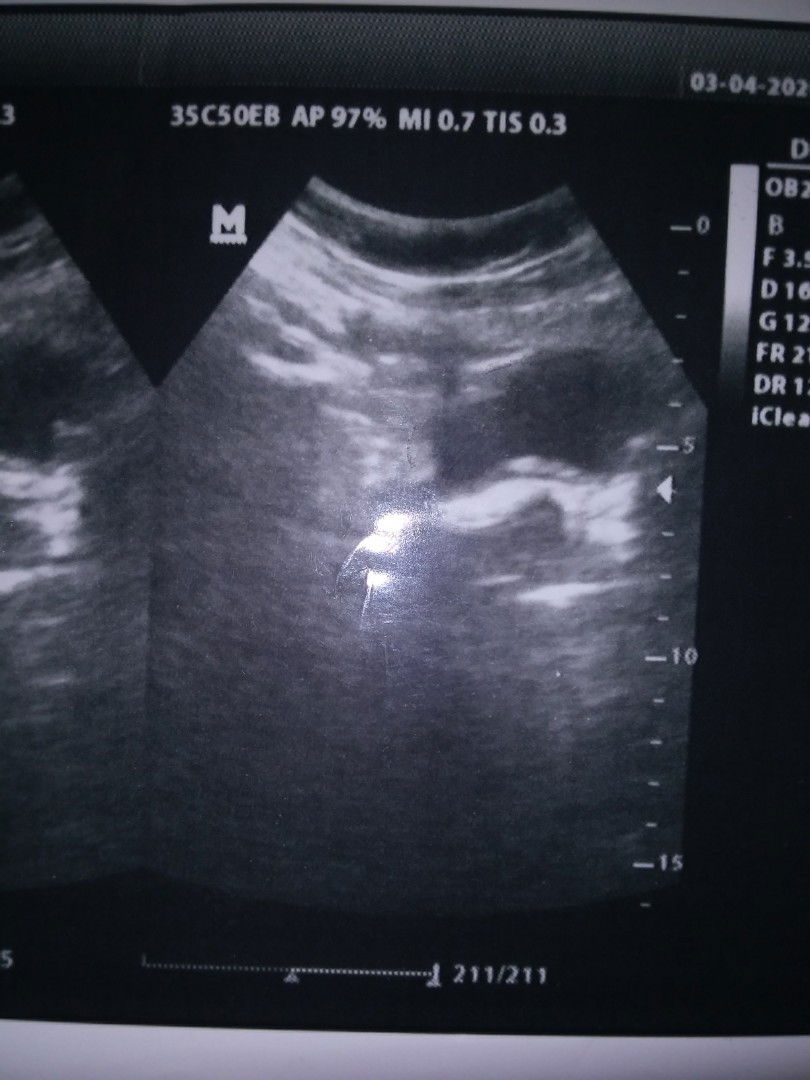

mau tanya bun .?? apa ini hamil kosong tapi kok ada putih" nya . aku udah telat 13 minggu .

Gimana ya bun

dokternya bilang ap bun? usg di temoat laun... nyari second oppinion